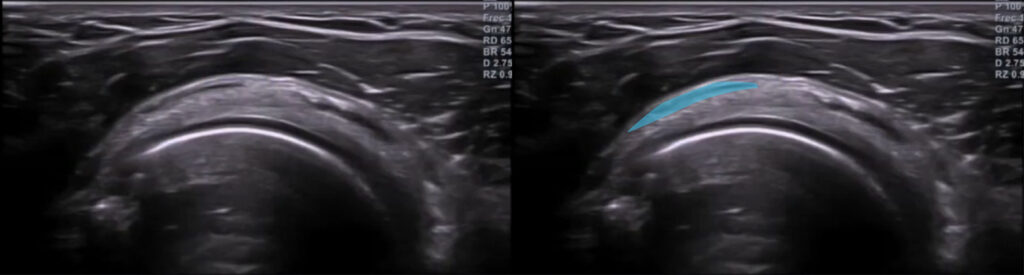

Utilizando el corte de referencia transversal del tendón supraespinoso, si hacemos barridos con lentitud, lograremos visualizar esta bursa.

La imagen no patológica, corresponderá a la siguiente (bursa señalada en azul):

En caso de patología, la imagen se vería de la siguiente forma:

Es común que la bursitis coexista con una tendinopatía del supraespinoso.